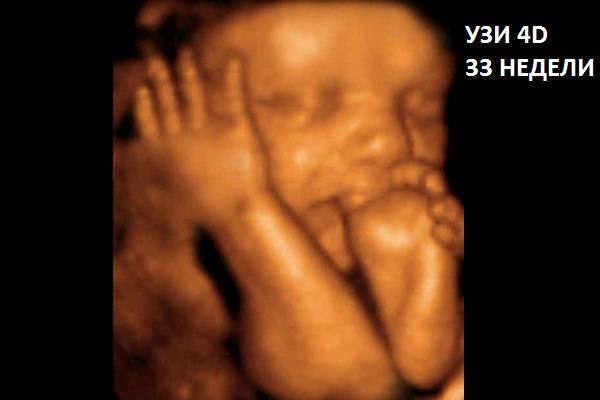

На УЗИ врач проверяет сразу несколько параметров. Они позволяют проверить правильность развития ребенка на 33-й неделе беременности, а также определить готовность матери к родам:

- предлежание ребенка;

- сердцебиение;

- размерные параметры;

- расположение пуповины по отношению к плоду;

- пол;

- количество плодных вод;

- степень созревания и толщина стенок плаценты;

- состояние матки и шейки матки.

Как выглядит ребенок на 33 неделе в 4D смотрите видео:

Нормы характеристик ребенка на 33-й неделе:

- головное предлежание плода;

- обычное количество околоплодных вод;

- плацентарная зрелость переходит от 1-й ко 2-й;

- внутренний и наружный зев закрыт;

- длина шейки матки более 3 см;

- печень и легкие имеют одинаковый размер и плотность;

- обвития пуповиной нет;

- бипатериальное значение равняется 76–90 мм;

- вес ребенка в норме варьируется в пределах 1800–2550 г;

- рост плода – 35–45 см;

- нос – 9–14 мм;

- окружность живота – 26–33 см;

- размер головы – 27–33 см;

- кость бедренная – 58–68;

- размер кости голени – 54–62;

- плечевая кость – 53–63;

- частота сердцебиения – 140–160 ударов в мин.;

- предплечье – 46–54.